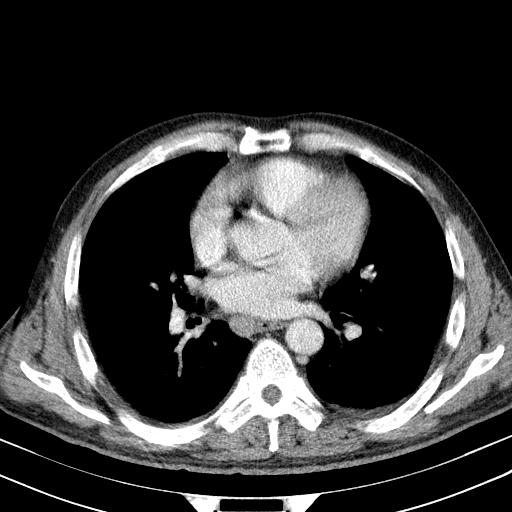

大家看看肝脏右叶片状低密度影是什么改变啊?

淋巴瘤?肝脏请增强后说啊

多发肿大淋巴结影,肝内改变需结合强化观察

多发肿大淋巴结影,肝内改变需结合强化观察。